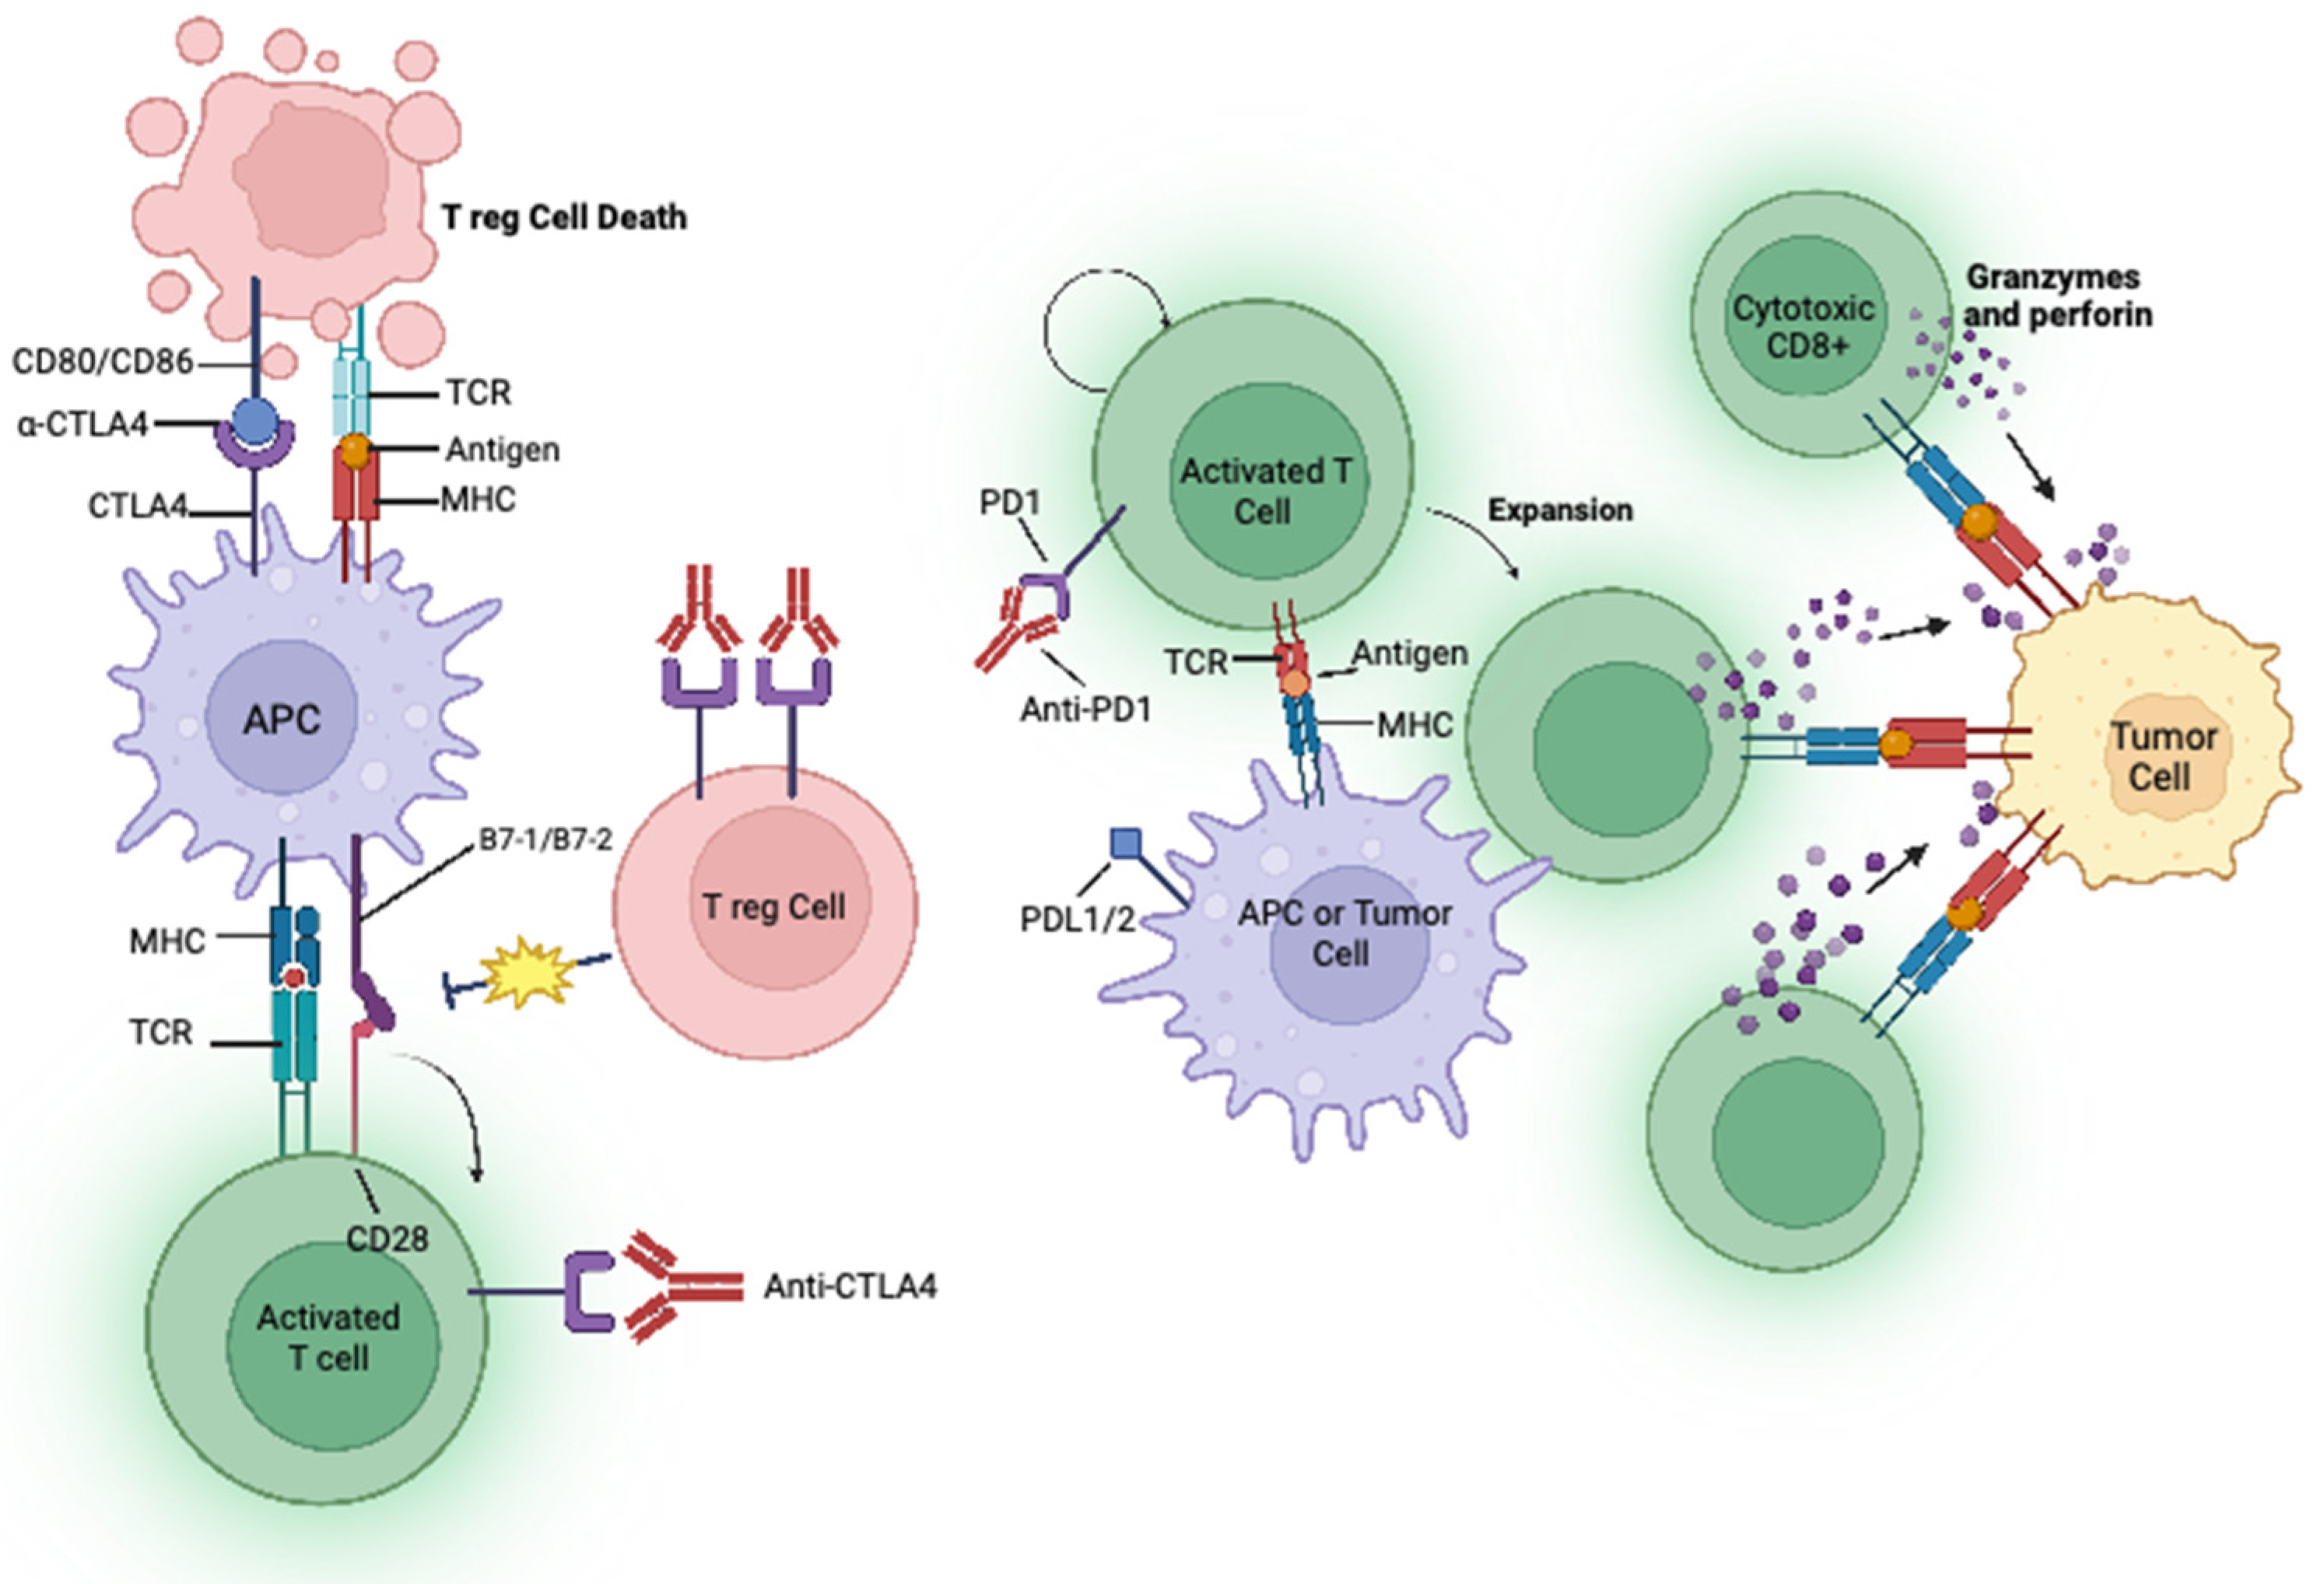

Prespecified interim analysis results from CheckMate 77T trial of neoadjuvant nivolumab or placebo plus chemotherapy and adjuvant nivolumab or placebo in stage II to IIIB NSCLC, as presented at ESMO Congress 2023 and reported by Clinical Care Options (CCO)